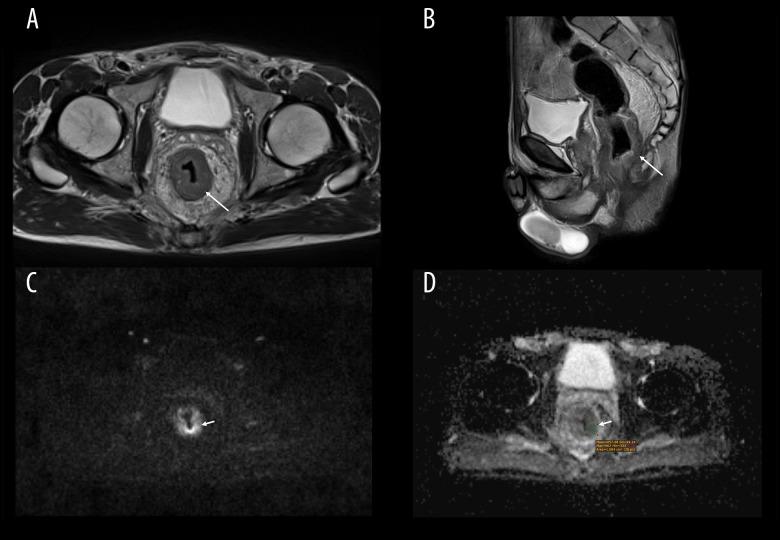

Diffusion-Weighted Magnetic Resonance Imaging of 103 Patients with Rectal Adenocarcinoma Identifies the Apparent Diffusion Coefficient as an Imaging Marker for Tumor Invasion and Regional Lymph Node Involvement.

BACKGROUND This retrospective study included 103 patients diagnosed with rectal adenocarcinoma at a single center in Poland who underwent preoperative diffusion-weighted magnetic resonance imaging (DWI) and aimed to determine whether the apparent diffusion coefficient (ADC) was an imaging marker for tumor invasion and regional lymph node involvement. MATERIAL AND METHODS We analyzed primary staging magnetic resonance examinations of the rectum of 103 consecutive patients with histologically proven non-mucinous adenocarcinoma who underwent surgical treatment. In 85 patients, surgery was preceded by long-course chemoradiotherapy (n=18) or short-course radiotherapy (n=67). The following DWI parameters were measured: ADC mean, minimum, maximum, and standard deviation in the region of interest (ADC SD-in-ROI). Values were compared between subgroups based on histological parameters from the report: tumor stage, lymph node stage, differentiation grade, the presence of extranodal tumor deposits, angioinvasion, and perineural invasion. Statistical analysis was performed using the Mann-Whitney U test and the unilateral t test. RESULTS ADC mean values were lower for cases in which postoperative histopathological examination lymph node invasion (P=0.04) and tumor deposits were found (P=0.04). Minimal ADC value was higher in cases in which tumor deposits were not found (P=0.009). ADC SD-in-ROI values were lower in cases in which lymph nodes invasion was confirmed (P=0.014). There were no statistically significant differences for other parameters. CONCLUSIONS The ADC values in pre-treatment DWI in patients with rectal adenocarcinoma were correlated with tumor invasion and regional lymph node metastases. Therefore, ADC values from the pre-treatment MRI may help plan adjuvant therapy in patients with rectal adenocarcinoma.